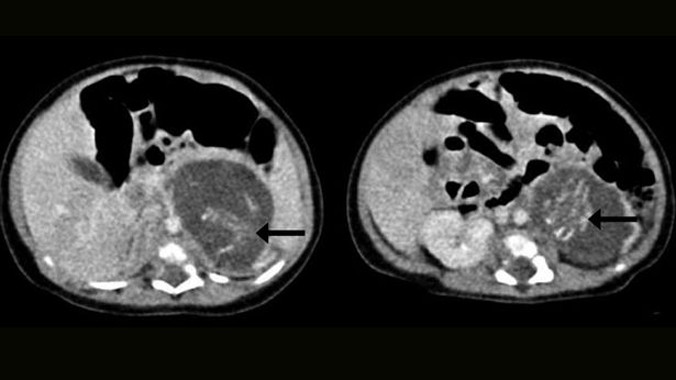

Chỗ mũi tên đánh dấu là xương sống của 2 thai nhi.

Con gái sơ sinh của cặp đôi người Hồng Kông mới ra đời ở bệnh viện Queen Elizabeth được 3 tuần đã phải trải qua một cuộc phẫu thuật để cắt bỏ hai phôi thai trong bụng. Chúng đã phát triển được khoảng từ 8 đến 10 tuần, hình thành đầy đủ dây rốn, tay, chân, xương sống, lồng ngực và cả ruột non. Trong đó, một phôi thai nặng đến 14.2 gram, cái còn lại nặng 9.3 gram. Ca phẫu thuật may mắn thành công, người ta đành phải từ bỏ cặp sinh đôi của “bà mẹ” 3 tuần tuổi, cô bé được cho xuất viện 8 ngày sau đó.

Bác sỹ Yu Kai-man – một cựu giáo sư trường đại học Trung Hoa ở Hồng Kông nói rằng đây là trường hợp bào thai lồng bào thai đầu tiên được ghi nhận tại thành phố mình. “Gần như không thể phát hiện ra có đến 2 thai nhi nữa ở trong cơ thể bé gái khi tiến hành siêu âm trước sinh bởi các phôi thai đó quá nhỏ” - vị chuyên gia phụ khoa và sản khoa cho hay.